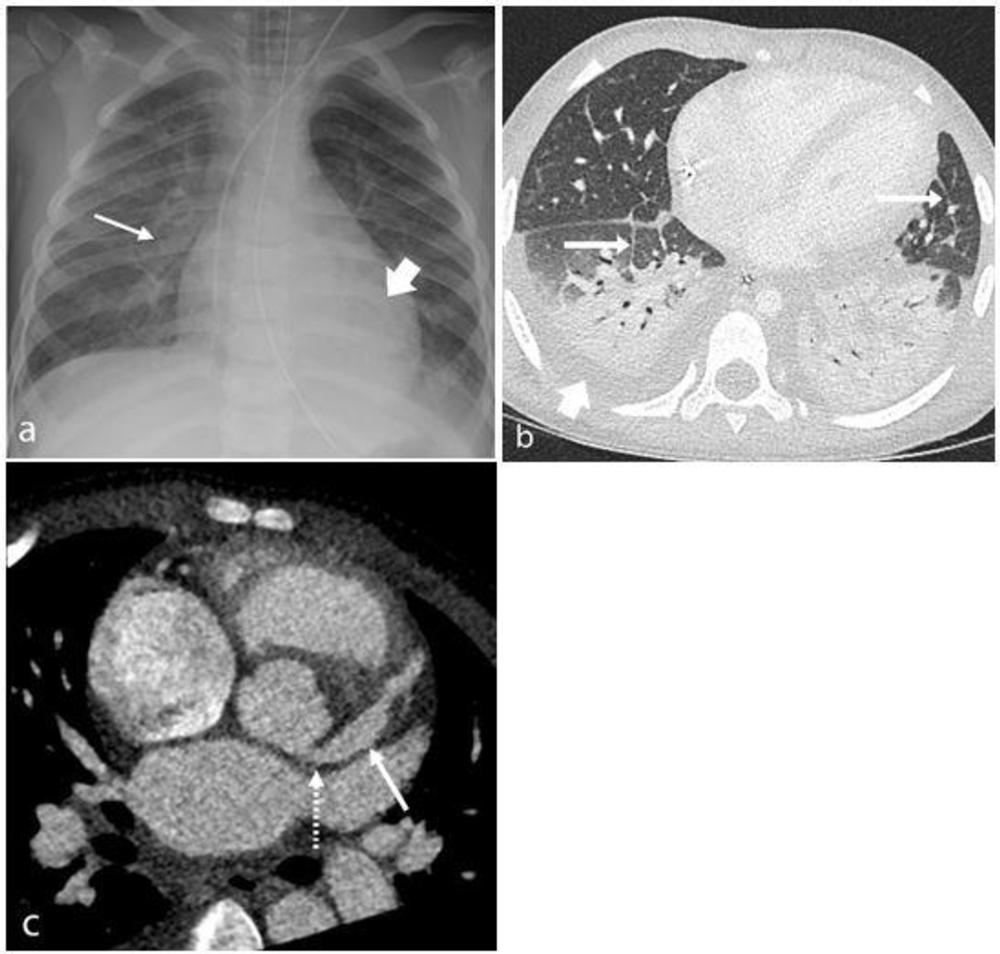

Figure 3. Range of cardiothoracic imaging findings in Multisystem Inflammatory Syndrome in Children (MIS-C). (a) Chest radiograph and (b) axial contrast-enhanced CT chest of a 4-year-old male presenting with fever, rash, abdominal pain, and diarrhea show features of pulmonary edema including perihilar interstitial thickening (thin arrow, a), septal lines (thin arrows, b), and pleural effusions (wide arrow, b). Left lower lobe collapse and consolidation (wide arrow, a) was also confirmed on CT (b). (c) 8-year-old boy with MIS-C noted to have impaired cardiac function and coronary artery aneurysms on echocardiogram. Contrast-enhanced cardiac CT demonstrating an axial view of the left main stem (LMS) (dotted arrow) and left anterior descending (LAD) (solid arrow) coronary arteries. There is medium sized aneurysmal dilation of the LMS (5.0 x 5.1mm z-score +2) and a large aneurysm in the proximal LAD (6.5 x 7.7mm z-score +13.9).

High-res (TIF) version